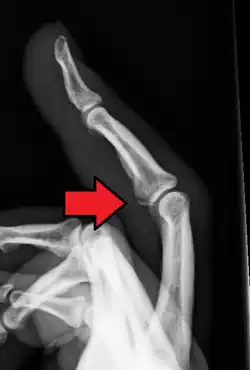

| Avulsion fracture of the proximal middle phalanx on the palm side | |